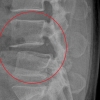

이완구 병역의혹 공개 검증 “차남 전방십자인대 재건수술 확실”

이완구의혹해명 “MRI·엑스레이 촬영도 응할 수 있어”